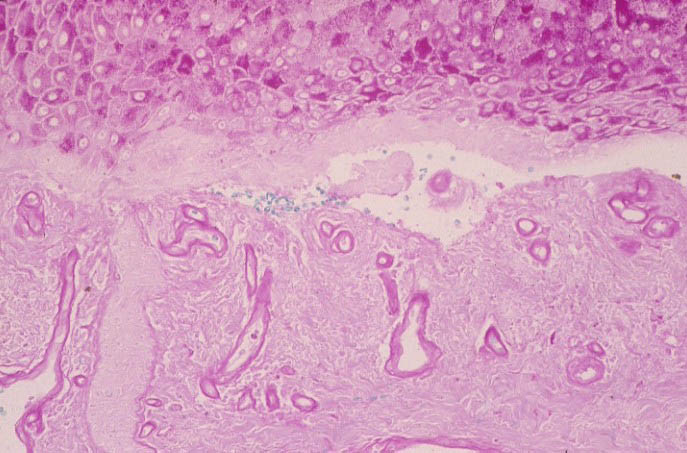

Atlas of skin histopathology

Hand blisters = حويصلات على اليدين